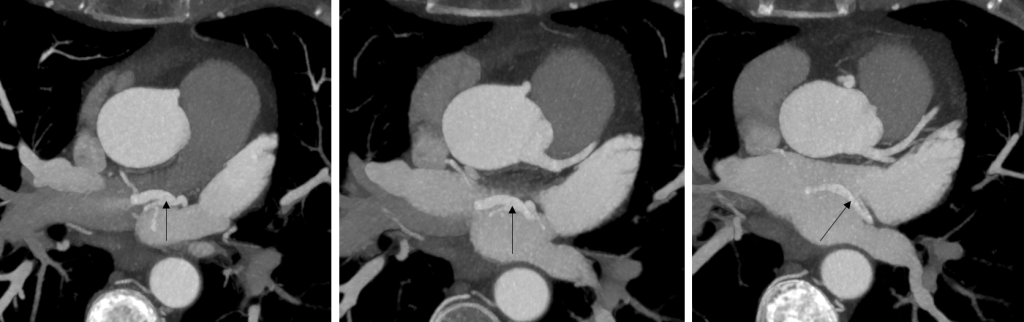

Figura 2: Fig 2 reconstrucţii axiale MIP (maxim intensity projection) din achiziţie angioCT coronariană

Discuţie caz nr 50: Examinarea angioCT coronariană este actual indicație de clasa 1 la pacienții cu boală coronariană cronică; este cazul unui pacient care a fost diagnosticat la examinare angioCT cu fistulă între arteră coronară dreaptă și arteră pulmonară dreaptă.